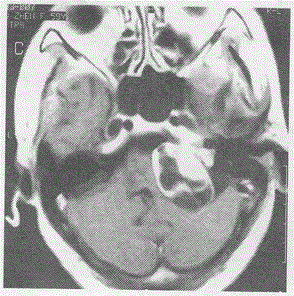

问题 女59岁,左耳听力下降一年,增强头颅MRI示

选项 A.脑膜瘤 B.海绵状血管瘤 C.听神经瘤 D.星形细胞瘤 E.动脉瘤

答案 C